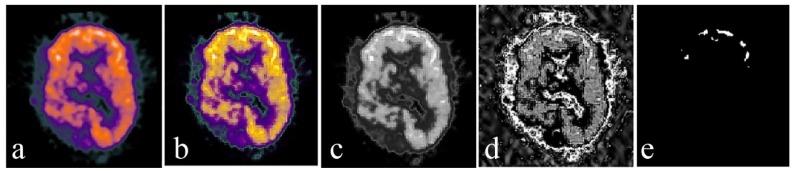

For the fusion of MRI gray scale images and PET color images, we used lesion region extracting based on the digital Curvelet transform (DCT) method. As curvelet transform has a better performance in detecting the edges, regions in each image are perfectly segmented. Curvelet decomposes each image into several low- and high-frequency sub-bands. Then, the entropy of each sub-band is calculated. By comparing the entropies and coefficients of the extracted regions, the best coefficients for the fused image are chosen. The fused image is obtained via inverse Curvelet transform. In order to assess the performance, the proposed method was compared with different fusion algorithms, both visually and statistically.

The analysis of the results showed that our proposed algorithm has high spectral and spatial resolution. According to the results of the quantitative fusion metrics, this method achieves an entropy value of 6.23, an MI of 1.88, and an SSIM of 0.6779. Comparison of these experiments with experiments of four other common fusion algorithms showed that our method is effective.

对于MRI灰度图像与PET彩色图像的融合,我们采用基于数字曲波变换(DCT)方法的病变区域提取。由于曲波变换在检测边缘方面具有更好的性能,每个图像中的区域都能被完美分割。曲波将每个图像分解为几个低频和高频子带。然后,计算每个子带的熵。通过比较提取区域的熵和系数,选择融合图像的最佳系数。通过逆曲波变换获得融合图像。为了评估性能,将所提出的方法与不同的融合算法在视觉和统计方面进行比较。

结果分析表明,我们提出的算法具有高光谱和空间分辨率。根据定量融合指标的结果,该方法的熵值为6.23,互信息(MI)为1.88,结构相似性指数测量值(SSIM)为0.6779。将这些实验与其他四种常见融合算法的实验进行比较表明,我们的方法是有效的。